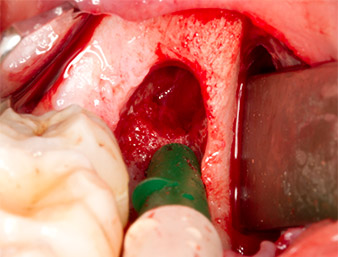

Um autogenes Material für die spätere Wundversorgung zu gewinnen, wurden mit einem piezochirugischen Instrument (Piezomed B5) gesunde Knochenspäne aus der Umgebung des Wurzelrests gewonnen (Abb. 5).

Piezomed B5

Abb. 5: Mit einem meißelförmigen piezochirurgischen Instrument (Piezomed B5) wird Knochen im Bereich der Alveole abgehoben. Dieser dient nach Entfernung des Wurzelrests als autologes Augmentationsmaterial

(vgl. Abb. 13 und 14).

Das autogene Gewebe wurde mit dem schaufelförmigen Arbeitsteil des Instruments entnommen und bis zur weiteren Verwendung in physiologischer Kochsalzlösung aufbewahrt (vgl. Abb. 13).

Um den Wurzelrest gewebeschonend frei zu präparieren, kam ein weiteres Instrument zum Einsatz (Piezomed S2), das primär für die Präparation des lateralen Fensters bei Sinusboden-Augmentationen indiziert ist. Zusätzlich wurden mit der diamantierten Kugel scharfe Knochenkanten geglättet (Abb. 6 und 7). Alle eingesetzten Piezomed-Aufsätze arbeiteten mit der jeweiligen automatischen Standardeinstellung ohne Booster-Funktion.

Piezomed S2

Abb. 6: Mit einem diamantierten kugelförmigen Instrument (Piezomed S2) wird der Wurzelrest vorsichtig frei präpariert, Knochenkanten werden geglättet.